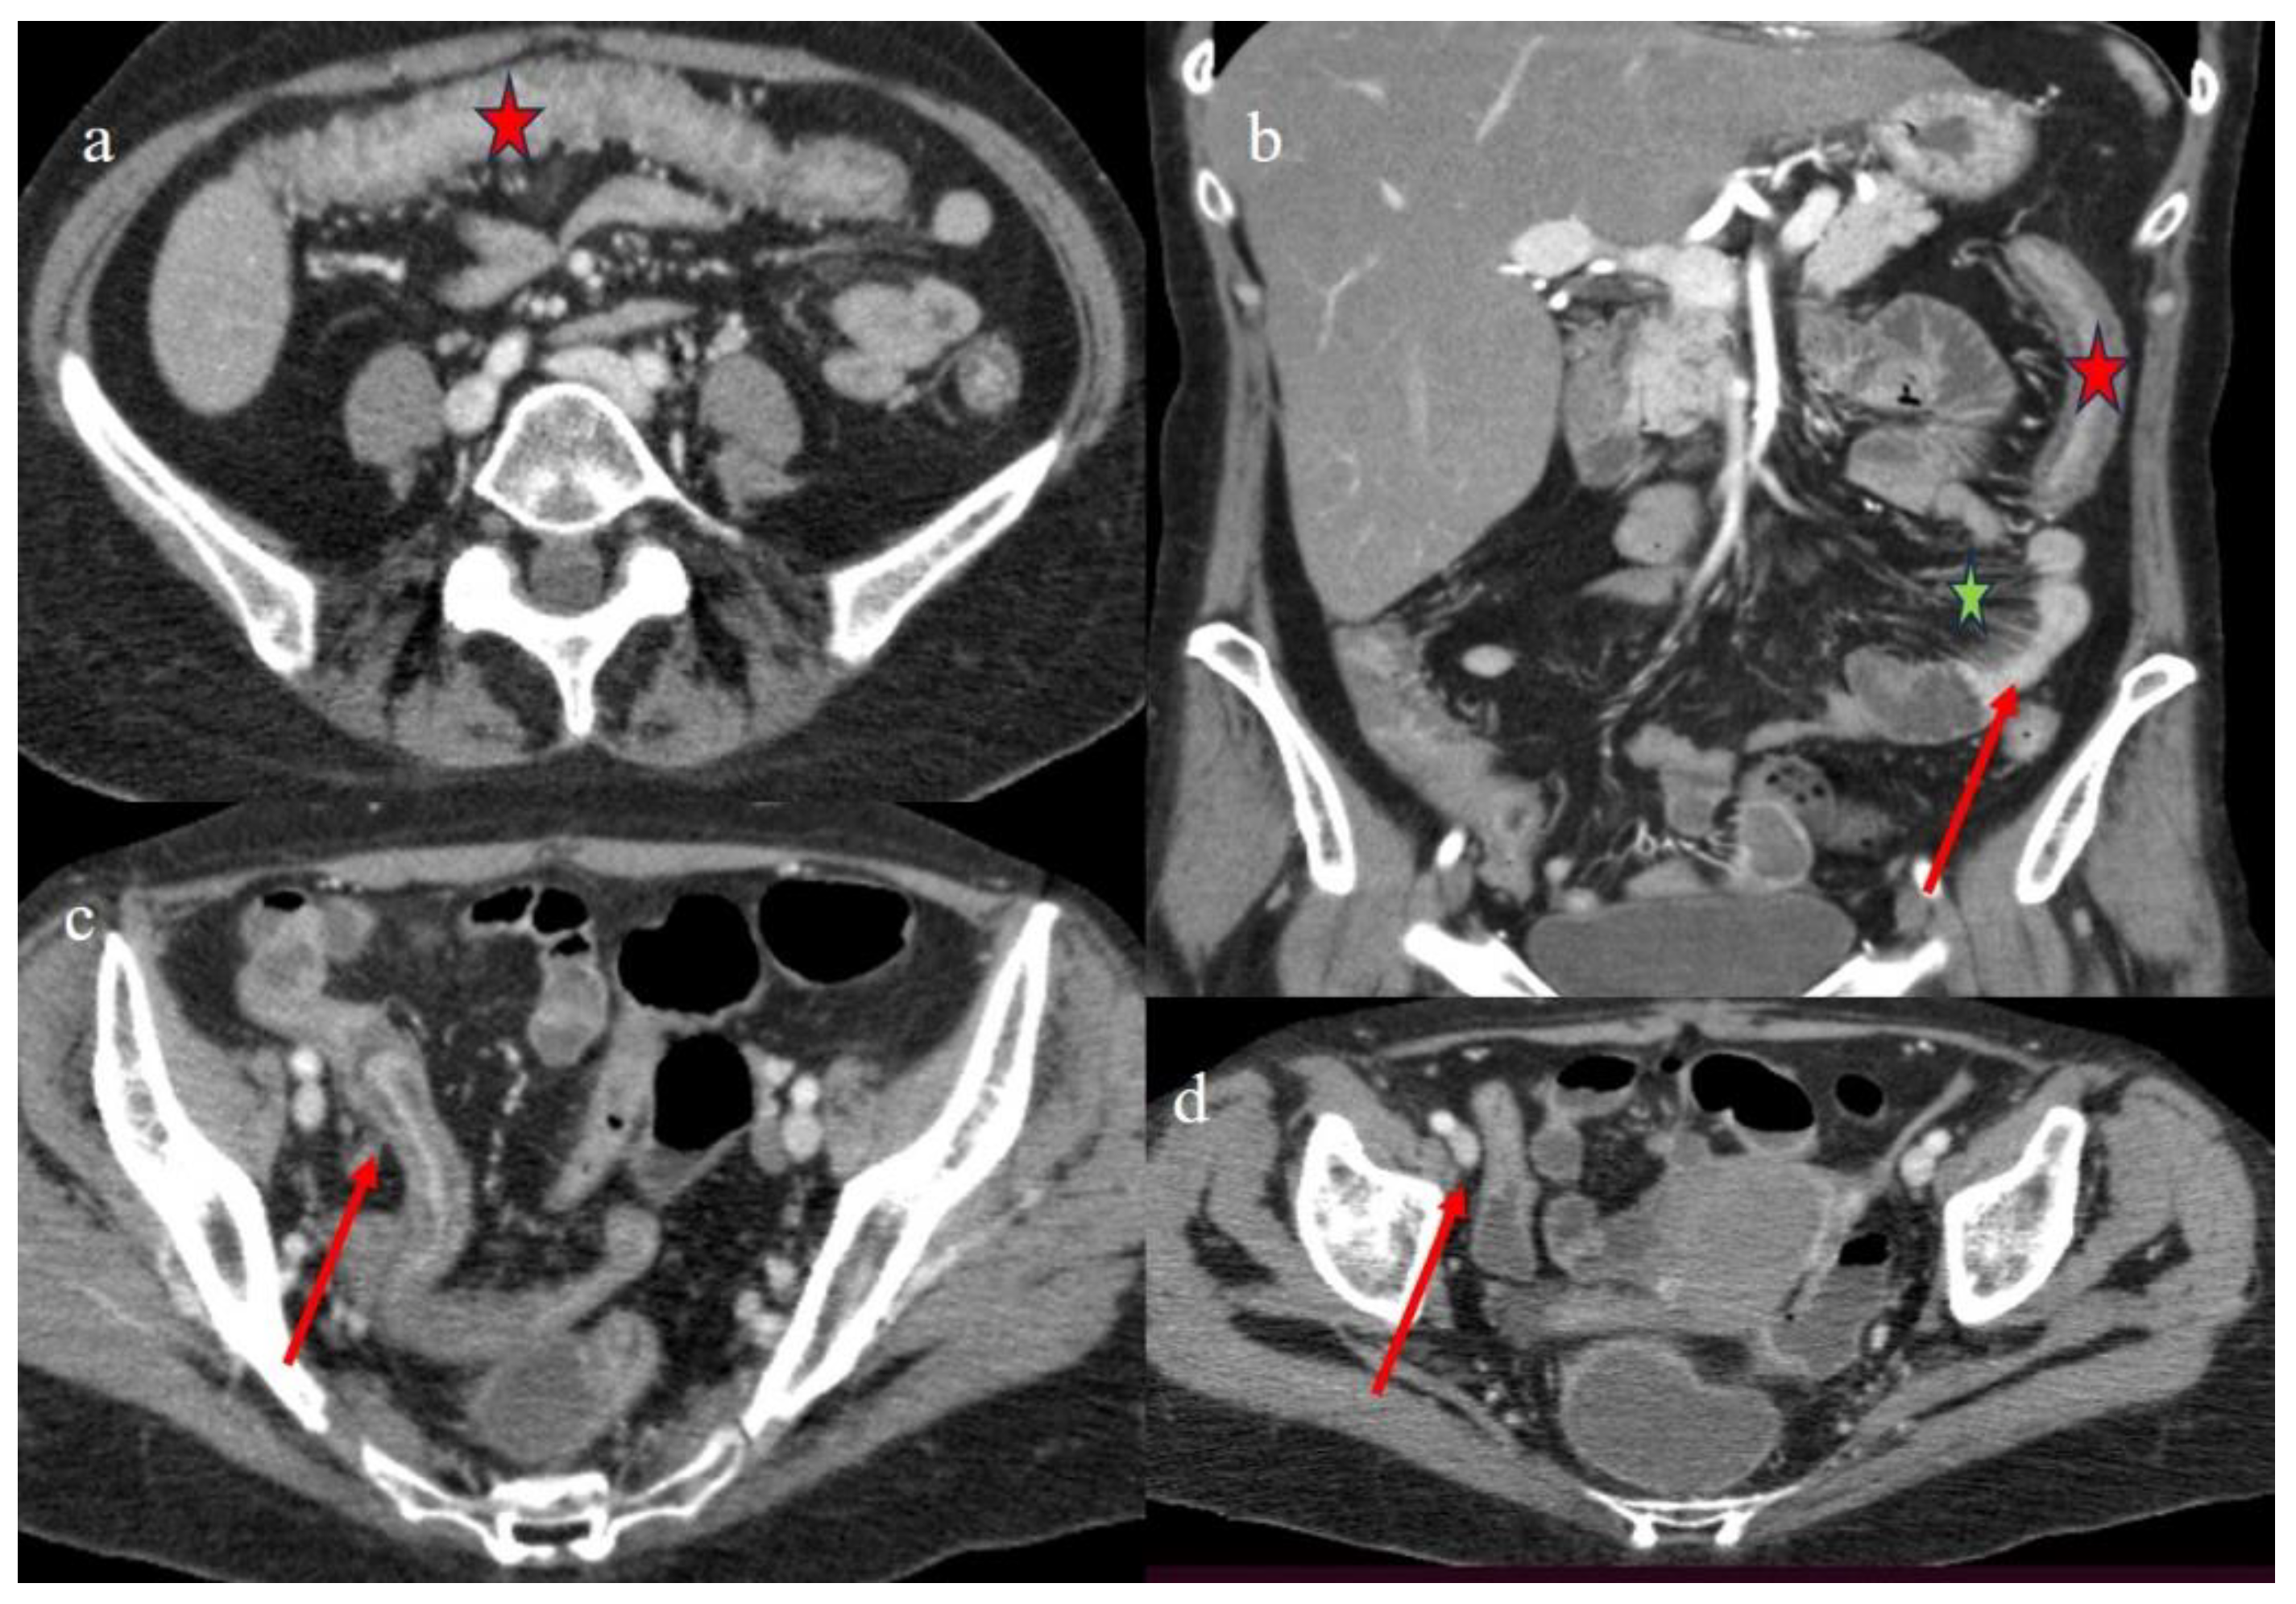

| 4 | P | P | Intestinal diffuse homogeneous thickness with homogeneous mucosal enhancement (on CECT control at 66 days after the HSCT); diffuse small bowel involvement with increased parietal thickness on CECT control at 120 days | Appearance of multisegmental thickness on sigma and descending colon and stratified enhancement on transverse colon on the CT FU at 120 days | Diffuse comb sign and poor reactive mesenteric lymph node | Mild gallbladder thickness and persistence of biliary tract dilatation on follow-up CT |